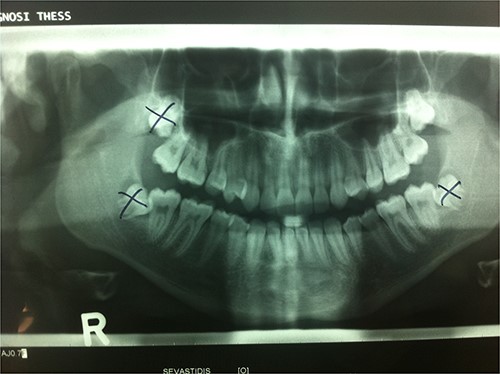

A 17-year- old male patient in good general health was referred to our Department of Oral and Maxillofacial Surgery, General Hospital Papanikolaou, Thessaloniki, Greece, with slight left facial swelling and discomfort. Patient history revealed that he had his third molars removed by a general dentist. Mandibular third molars and right maxillary third molar were removed uneventfully (Fig. 1). However, during the extraction of the left maxillary molar, the tooth disappeared from the surgical field and the attempts of the dentist to find and remove the displaced tooth remained unsuccessful.

Orthopantomograph showing the location of third molars before their removal. The left maxillary third molar was displaced into the ipsilateral infratemoral fossa.